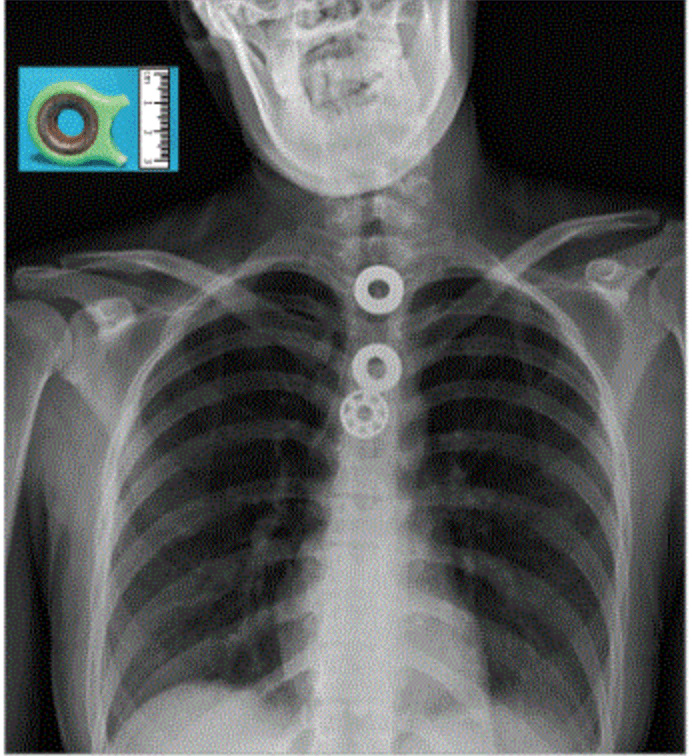

研究人员曾考虑过规格为2x4 (即宽度为2个凸粒,长度为4个凸粒) 的乐高积木,不过因为有长方形直角,容易有刺穿风险,后来便想到了乐高迷你小人的头部配件,大小比玉米粒大一些,而且又是圆滚滚的,不容易伤害内脏。

实验用到的乐高小人头尺寸数据,单位毫米。丨来源:参考文献[6]